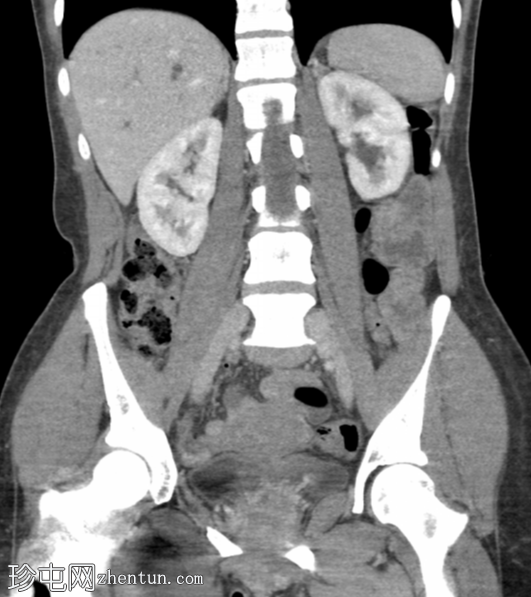

冠状位增强扫描(门静脉期)

肝内和肝外胆管中度扩张,胆总管(13 mm)内可见一小块边缘不透光结石(8 mm)。

胆囊壁轻度增厚,可能继发于慢性胆囊炎。未见管腔内结石。

双侧输卵管结扎术。

右侧股骨动力髋螺钉。